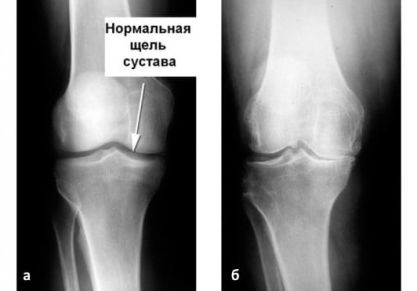

Деформирующий артроз коленного сустава 1, 2, 3 степени: причины, симптомы, лечение

Что представляет собой деформирующий артроз коленного сустава, по каким причинам появляется заболевание. Симптомы и признаки, лечение 1,2,3 стадий.